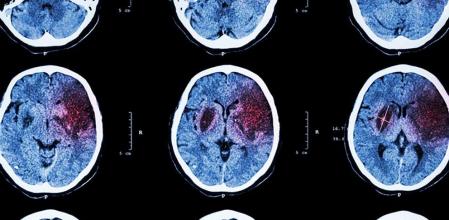

Lo primero es hacer el examen físico y realizar un análisis de sangre para tener más información sobre los coágulos y descartar posibles infecciones. También se suele hacer una visión por tomografía computarizada que puede ayudar a detectar si hay un tumor y una resonancia magnética que determinará el tejido cerebral afectado. Hay una variedad grande de pruebas. Otra de las más frecuente es la angiografía cerebral que consiste en introducir un catéter en el cuerpo, usualmente a través de la ingle, y recorrer las arterias.